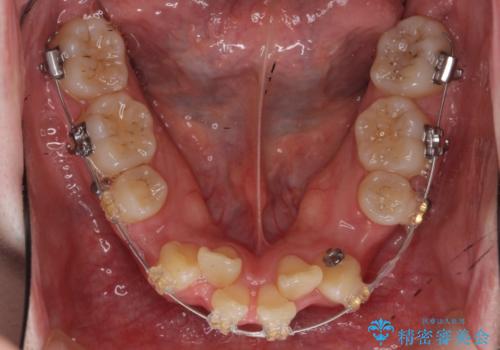

- ワイヤー矯正

- 3年8ヶ月

- 10-30回

- 前歯のがたつき、前突を主訴に来院。

通常前から4番目の歯を抜歯するのですが、左上5番の形が矮小であったため、そちらを抜歯しました。(患者様の希望にそっています。)

前から5番目の歯を抜くと、長くて1年ほど矯正期間が延長しますが、形に異常がない左上4番を抜かずに保存しています。